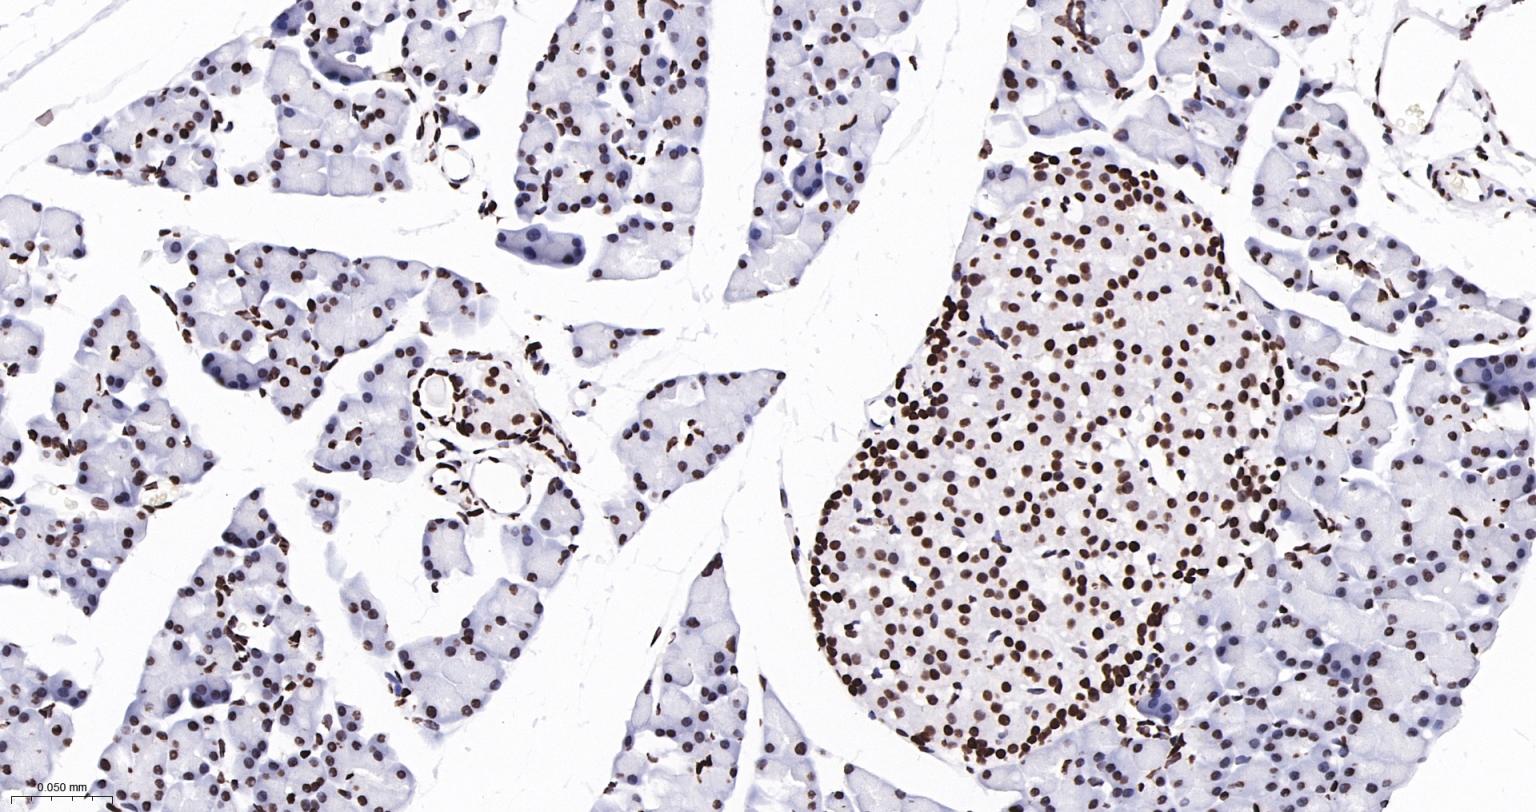

Paraformaldehyde-fixed, paraffin embedded Human Colon Cancer; Antigen retrieval by boiling in sodium citrate buffer (pH6.0) for 15 min; The section was incubated with Acetyl-Histone H3(K9) Monoclonal Antibody, Unconjugated (bsm-63244R) at 1:200 overnight at 4°C, followed by conjugation to the bs-0295G-HRP and DAB (C-0010) staining.